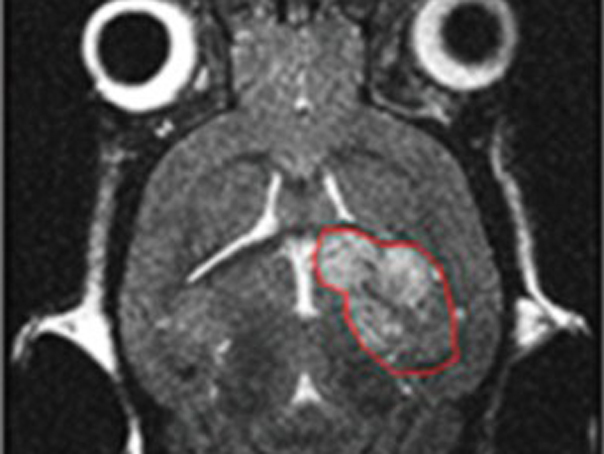

În mod normal, proteina RAS ajută la dezvoltarea celulelor, însă aceasta poate să cauzeze şi o creştere incontrolabilă a celulelor “mutante” sau neregulate. Ca rezultat, RAS joacă un rol important în dezvoltarea unor forme de cancer, în special cel pancreatic.